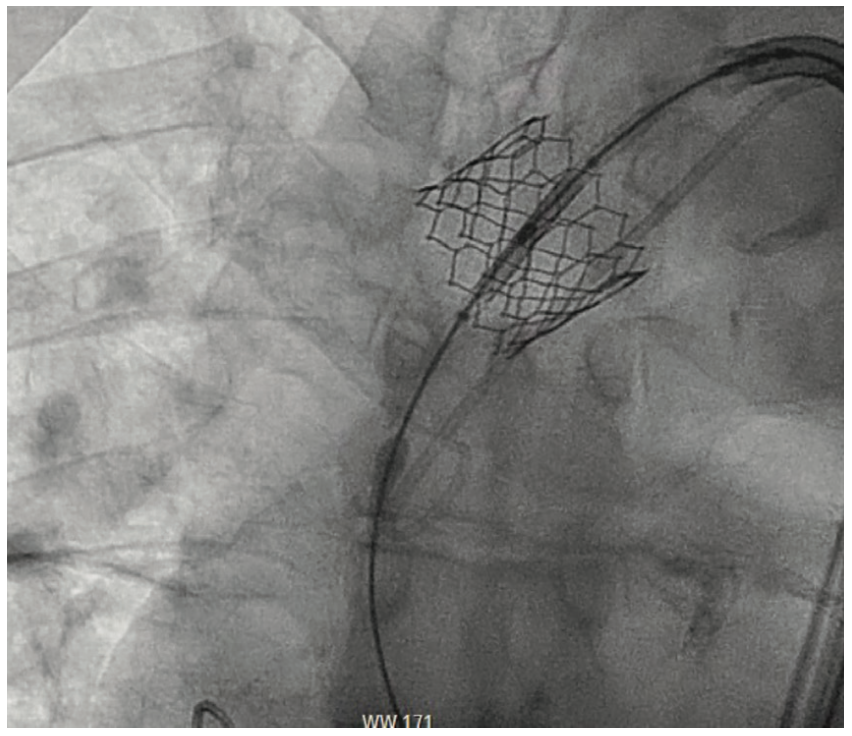

Aortic angiogram of TAVR valve post deployment (red arrow). (A) Safari Tavr Valve Embolization Aortic valve replacement (avr) is the only effective therapy. Embolization of transcatheter aortic valve replacement (tavr) prostheses is a rare and serious procedural complication. Transcatheter valve embolization and migration (tvem) are potential complications of transcatheter aortic valve implantation (tavi) (1). Aortic stenosis (as) is a common valvular heart disease, especially prevalent in the elderly population, and symptomatic severe as. Capture. Tavr Valve Embolization.